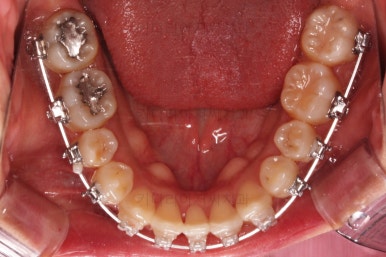

아랫니는 최대한 추가 발치 없이 후방의 송곳니를 당겨와서 앞니 역할을 하게 했습니다.(총 4개 앞니처럼)

부분적으로 장치 셋팅을 다시 해줬고요.

밀고 당기기를 위해서 미니스크류를 셋팅했고요.

교합과 중앙선 및 디테일을 맞춰 나갑니다.

중앙선, 교합, 앞니 맞물림 등 모든 것이 좋아졌네요.

교합, 정중선 모두 좋아졌고요.